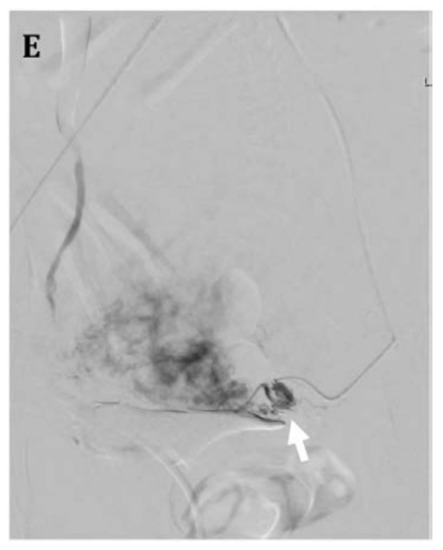

4.3. Uterine Artery Embolization